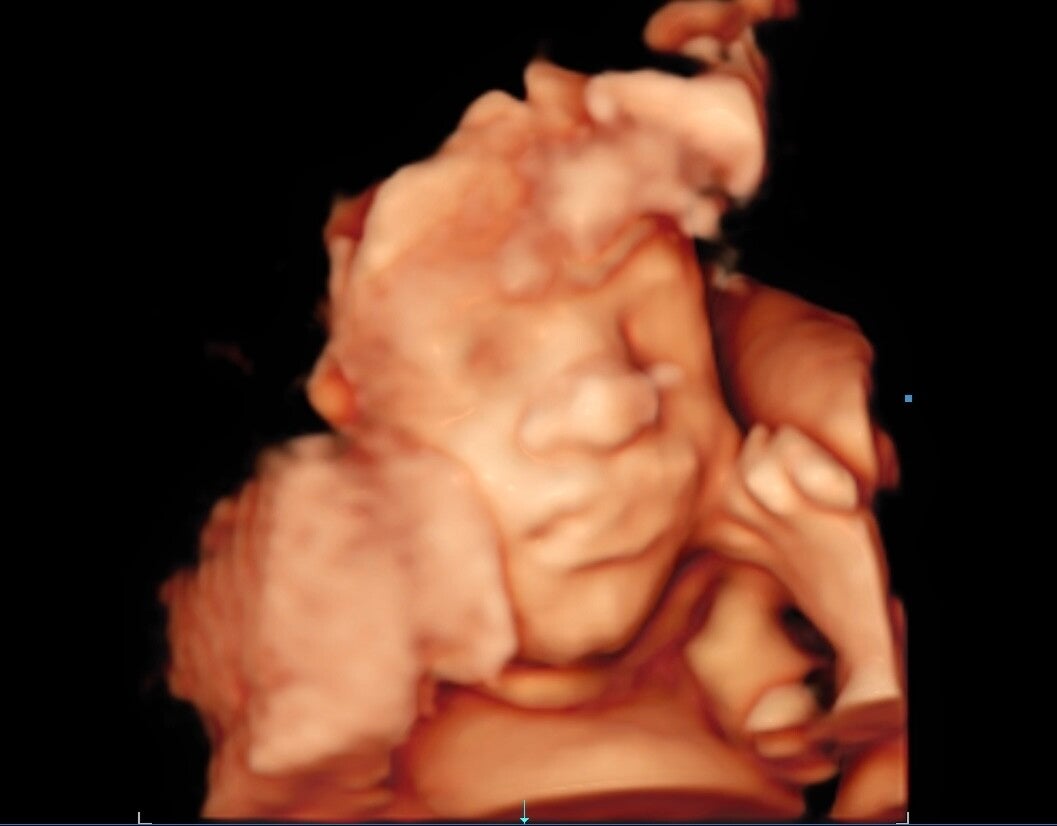

4D ECHO

Een 4D echo is een 3D echo met bewegende beelden om jou kindje live te zien. Dit is de nieuwste techniek qua echografie. De ultrasone geluidsgolven kunnen direct omzetten naar 4D beeld waardoor je de baby ‘live’ kunt zien. Je kunt nu de baby zien bewegen, gapen of zelfs lachen.

Na afloop van de pretecho krijg je de beelden mee naar huis en kun je ze thuis nogmaals bekijken. Het is een hele unieke en geweldige ervaring om zo'n

live video te zien van jou kleine wondertje. Net als bij een 3D echo is de hoeveelheid vruchtwater een belangrijk aspect voor de kwaliteit van de beelden, maar ook de ligging van de placenta en beweeglijkheid van het kindje. Wij raden dus aan om net als bij de 3D echo tussen de 25e en 30e week bij ons te komen voor een 4D echo.